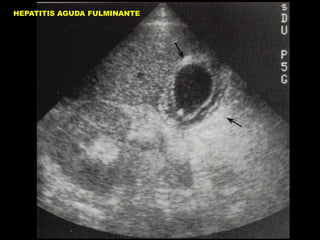

CI HEPATICO CON ASCITIS

INSUFIECIENCIA HEPATICA

HEPATITIS AGUDA FULMINANTE